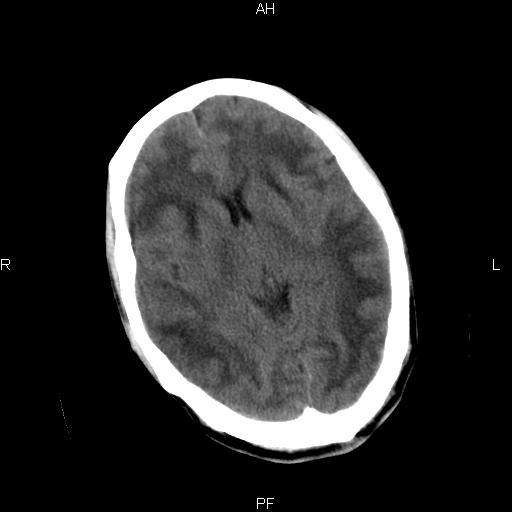

男性,45岁,缄默少语,四肢无力一个月。骨窗未见明确异常。

弥漫性脑白质低密度症

对称性脑白质广泛低密度。有高血压史及大量饮酒史吗?

考虑重度脑白质稀疏症。

双侧弥漫性对称性全累及性(外囊亦有累及)脑白质病

患者病程月余,脑沟裂闭合,第三脑室较窄,提示应该有较明显的脑白质水肿,考虑有持续性炎性病变

综合考虑脑白质感染性或非感染性炎症可能性大,不排除为克雅氏病